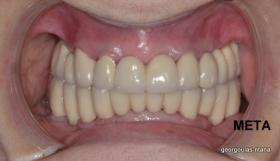

ΟΛΙΚΗ ΑΠΟΚΑΤΑΣΤΑΣΗ ΑΝΩ Κ ΚΑΤΩ ΓΝΑΘΟΥ ΜΕ ΕΜΦΥΤΕΥΜΑΤΑ, ΑΜΕΣΗ ΦΟΡΤΙΣΗ Κ ΑΝΟΙΚΤΗ ΑΝΥΨΩΣΗ ΙΓΜΟΡΕΙΟΥ

Η ασθενής αυτή είχε παλιές ακίνητες αποκαταστάσεις (γέφυρες) στην άνω γνάθο  κ μια κινητή προσθετική αποκατάσταση (μερική οδοντοστοιχία-"μασελάκι") στην κάτω γνάθο. Ήταν δυσαρεστημένη τόσο με την εμφάνιση όσο και με τη λειτουργία των δοντιών της καθώς παραπονιόταν ότι  είχαν εντονη κινητικότητα ενώ και οι προσθετικές τους εργασιές δεν ήταν σταθερές. Η πρόγνωση των δοντιών κρίθηκε φτωχή με αποτέλεσμα να μην είναι δυνατή η συμμετοχή τους σε μια νεα προσθετική αποκατάσταση με μακροχρόνια διάρκεια. Η ασθενής επιθυμούσε οι νέες αποκαταστάσεις να είναι σταθερές και ακίνητες.  Για το λόγο αυτό αποφασίστηκε η ολική αποκατάσταση της άνω κ κάτω γνάθου με ακίνητες επιεμφυτευματικές εργασίες. Στην αριστερή πλευρά της άνω γνάθου, λόγω μη επαρκούς οστού για την τοποθέτηση εμφυτευμάτων προηγήθηκε επέμβαση ανοιχτής  ανύψωσης ιγμορείου άντρου με τη χρήση πιεζοχειρουργικού μηχανήματος ώστε να δημιουργηθεί το κατάλληλο οστικό υπόστρωμα. Ακολούθησε σε επόμενο χειρουργείο η εξαγωγή των υπάρχοντων δοντιών κ η άμεση τοποθέτηση εμφυτεύματων (άμεση εμφύτευση) κ δύο μέρες μετά η τοποθέτηση προσωρινής εργασίας επί των εμφυτευμάτων (άμεση φόρτιση) με αποτέλεσμα η ασθενής να μη μείνει καθόλου χωρίς δόντια κ να είναι καλυμένη αισθητικά όσο καιρό διήρκησε η εργασία